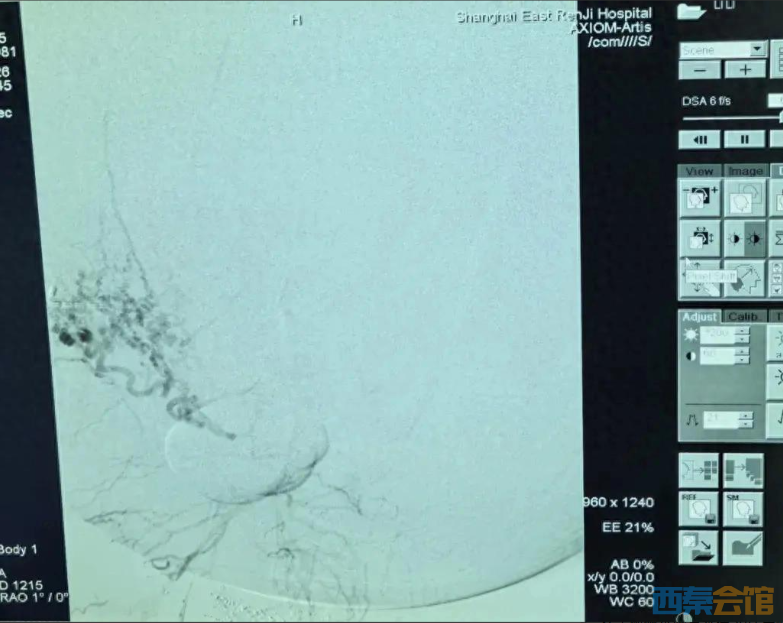

第一棒交给肿瘤介入科主任张学彬。在DSA(数字减影血管造影)的精准引导下,张学彬凭借娴熟的技术,成功找到并栓塞了肿瘤的多支滋养动脉,为后续手术清除了最大的“路障”。